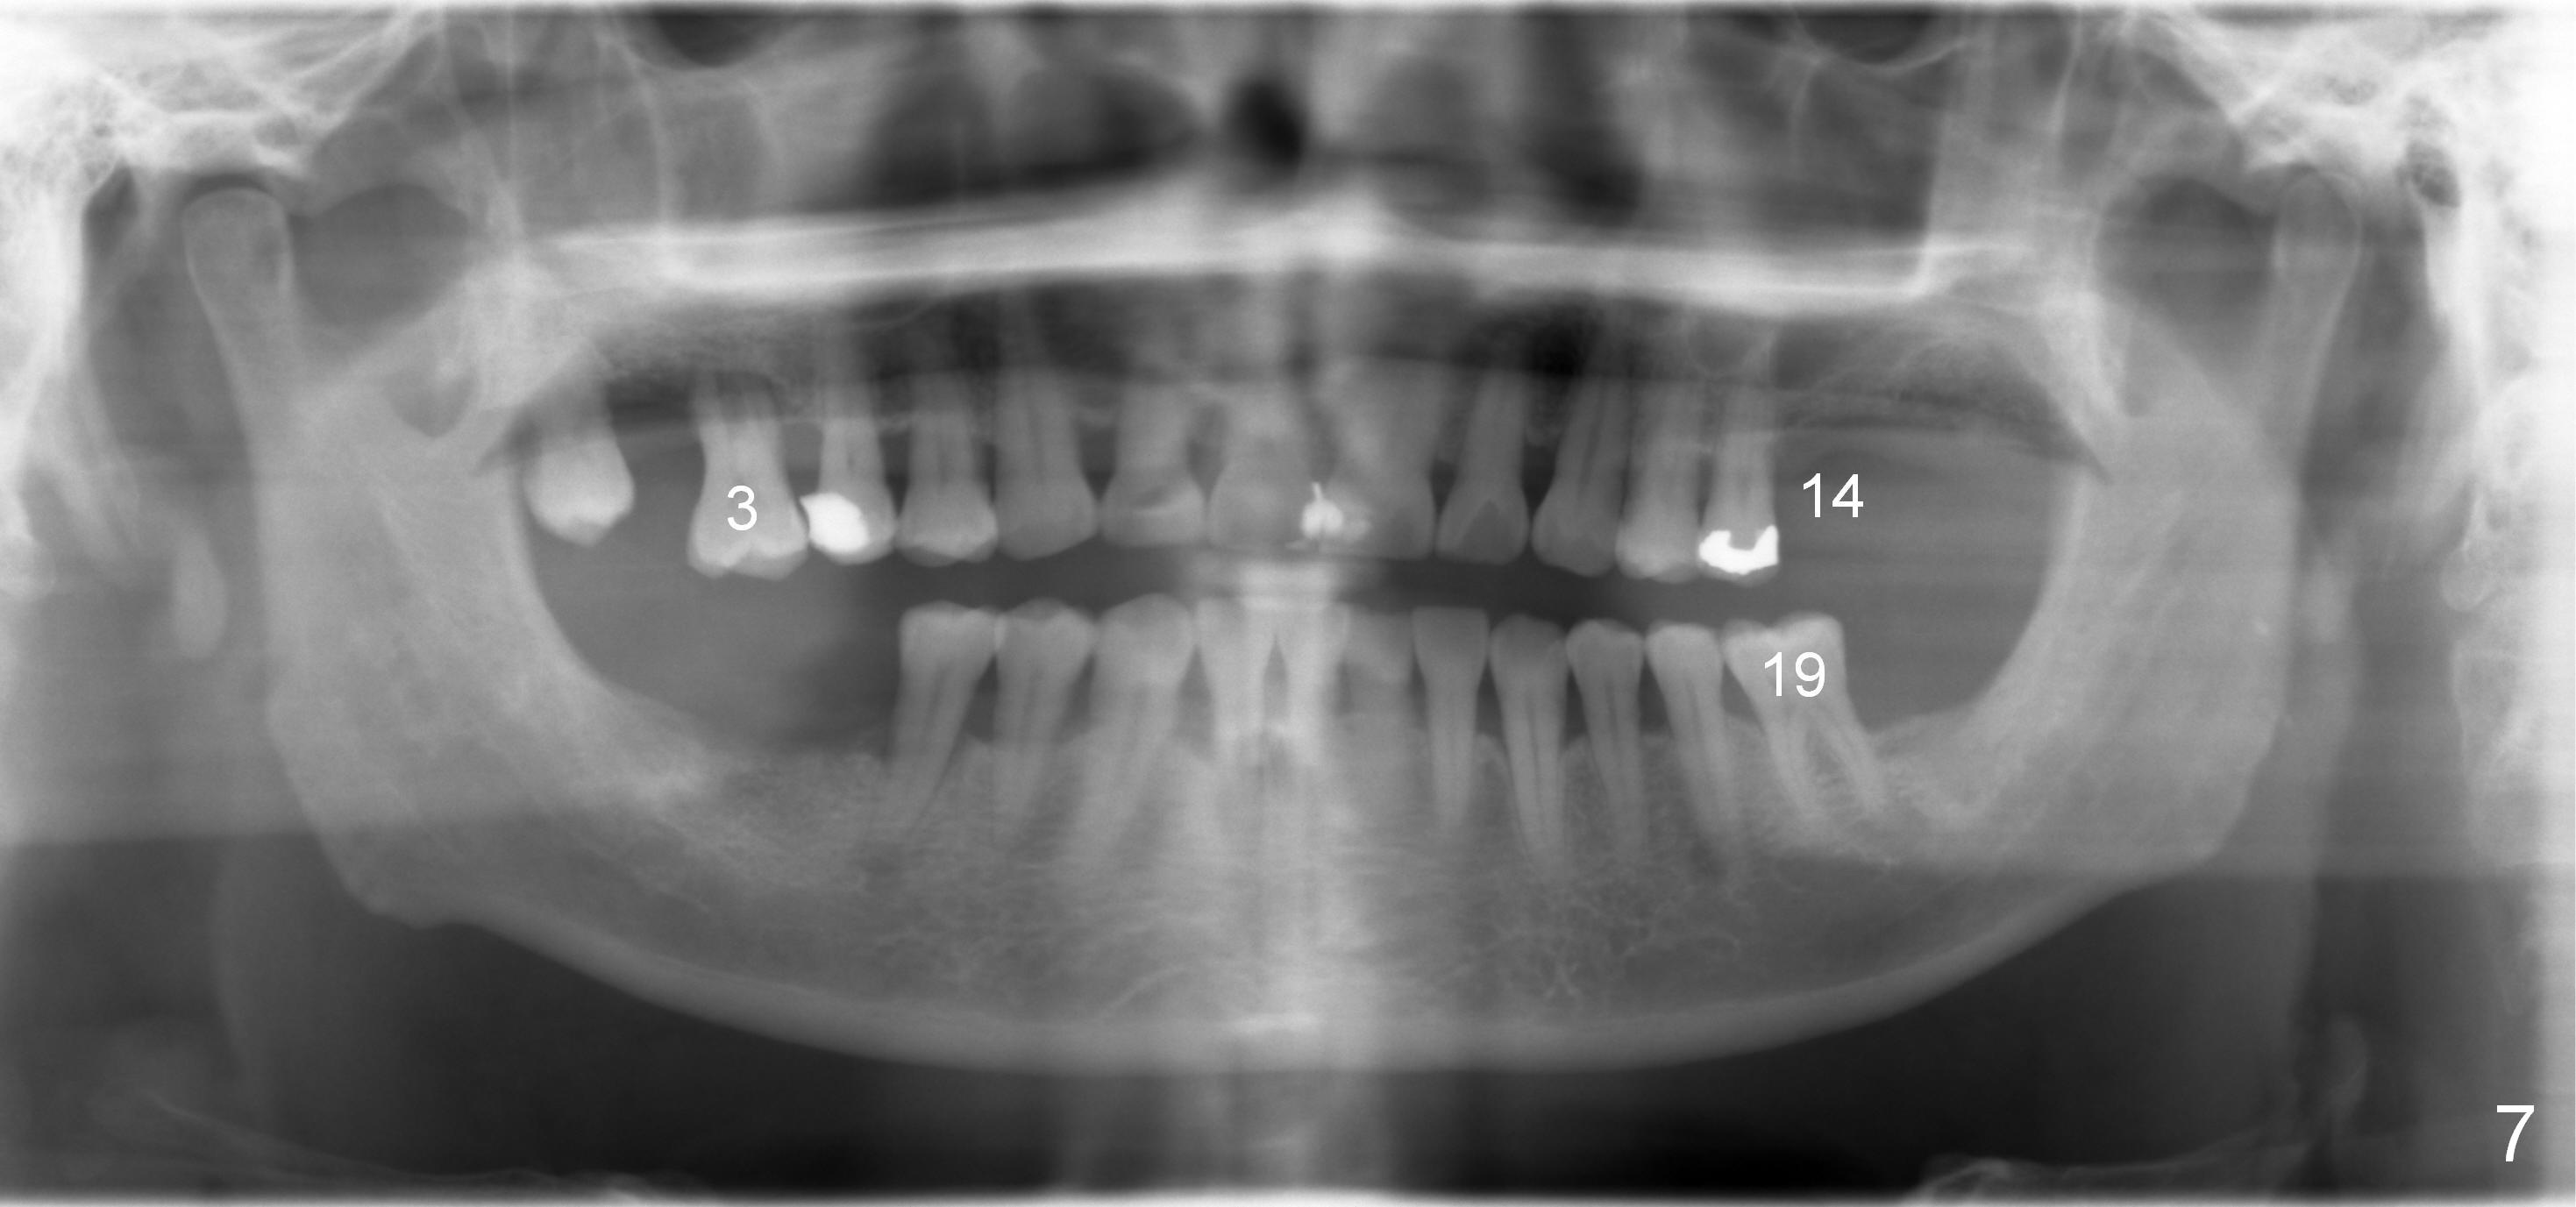

A 60-year-old man requests implant at the site of #14 (Fig.1,2, opposing a natural tooth (Fig.7)). Although bone height is limited, bone density appears high with sinus septi (S and arrowheads). The ridge seems to be wide clinically; implant will be as wide as possible. An envelop incision will be made to get the best visibility (as compared to tissue punch). At entry point, the bone height is 2.5 mm (Fig.3 red line); as the implant or osteotomy diameter increases, bone contact enhances (pink lines). If lateral window approach is adopted, a longer implant will be chosen (14 mm in Fig.3 vs. 11 mm in Fig.4, both tissue-level). The stronger distal septum may deviate the apical portion of the longer implant (Fig.3 arrow).